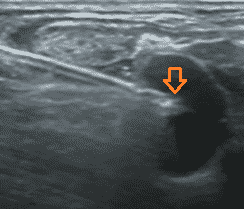

La ecografía: una herramienta imprescindible en la colocación de reservorios

Muchos estudios han demostrado que la técnica ecoguiada para colocar dispositivos venosos totalmente implantados es segura y eficaz. Es hoy en día, un recurso indispensable que mejora de forma considerable el éxito en la primera punción y reduce drásticamente los riesgos relacionados con la misma.

Como ejemplo, el estudio Canfora et.al, llevado a cabo sobre inserciones en vena yugular interna derecha concluye que la ecografía ha mejorado la seguridad y la eficacia de las colocaciones de dispositivos de acceso venoso.

La técnica con ultrasonido se ha convertido en el método de rutina para el cateterismo de la vena yugular interna (VYI) reduciendo drásticamente las tasas de fracaso y complicaciones para la colocación del reservorio venoso.

2. Fundamentos ecográficos a conocer para acceder a la vena

Existen 2 técnicas principales:

- Out of plane: fuera de plano o plano transversal

- In plane: en plano o plano longitudinal

En ciertos casos es posible usar una técnica que combina las 2 anteriores: se trata de un tener una aproximación longitudinal de la aguja en un plano transversal:

El acceso a la vena yugular se realiza bajo control ecográfico mediante abordaje lateral con una curva más fisiológica del catéter.

La sonda es ortogonal a la vena pero la aguja es paralela al eje principal de la sonda, como visto anteriormente.

Esto hace que sea mucho más fácil seguir la aguja en casi todo su recorrido:

Nunca se debe pinchar la pared posterior de la vena, es decir nunca se debe hacer transfixión. Esto evita la punción arterial de la arteria carótida